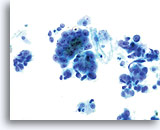

Abnorme Endometriumzellen (NOS)

(51-jährige Patientin, letzte Periode unbekannt). Abgebildet ist ein lockerer Verband aus Zellen mit erhöhter Kern-Plasma-Relation, unregelmäßigen Kernmembranen und grobem, etwas aufgehelltem Chromatin.

60x

Biopsie -Benignes proliferierendes Endometrium

Abnorme Endometriumzellen (NOS)

(51-jährige Patientin, letzte Periode unbekannt). Abgebildet ist ein lockerer Verband aus Zellen mit erhöhter Kern-Plasma-Relation, unregelmäßigen Kernmembranen und grobem, etwas aufgehelltem Chromatin.

60x

Biopsie – Benignes proliferierendes Endometrium